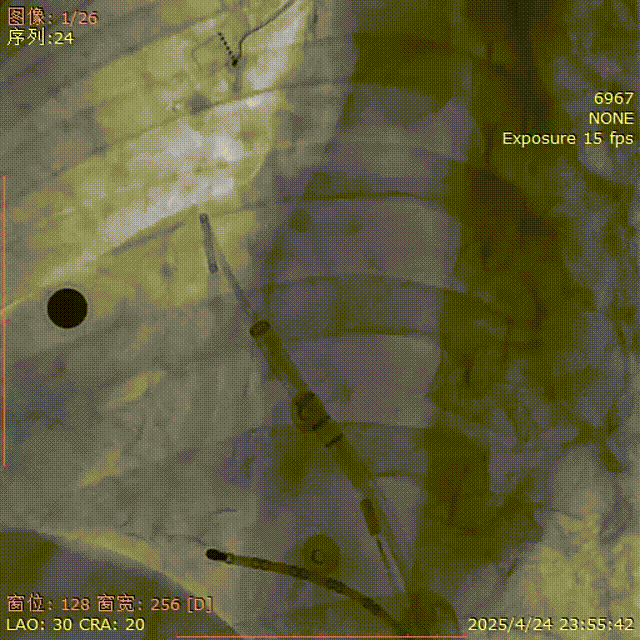

肩位造影

LAO 30° CRA 20°

心耳分析

“菜花型”心耳,远端梳状肌发达,共干长度不足,可用深度较浅,上分叶轴向良好;

肝位开口:25mm;深度: 24mm

选伞:FLX 31mm